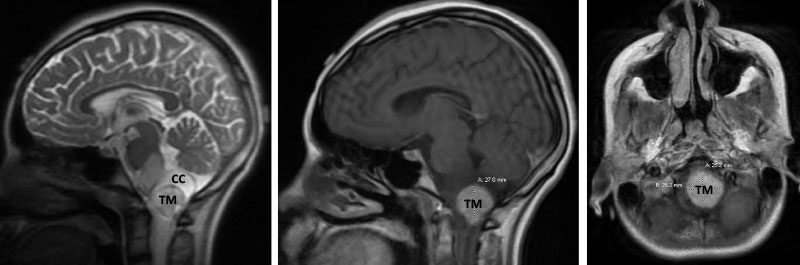

Figure 3. Immediate post-op CT (left) and two-year follow-up MRI (right).